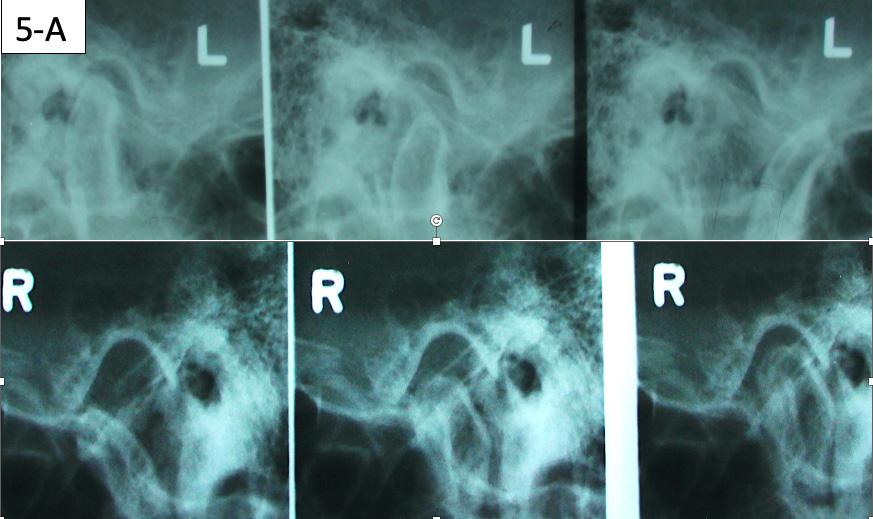

The patient had the following: migraine headaches, sore teeth upon awakening, buzzing in his ears, teeth clenching and grinding, joints locking when opened wide, popping, and clicking, pain and problems sleeping soundly. He had normal range of motion, deviation to the right on opening, clicking, The patient also had a sensitivity to palpation on the right TMJ, Posterior neck left, Trapezius left and Anterior digastric bilaterally. The transcranial TMJ radiogram reveals posteriorly displaced condyles and limited maximum opening on the right side (Figure 5-A).

FIG. 5A: Pre-treatment, TMJ radiogram